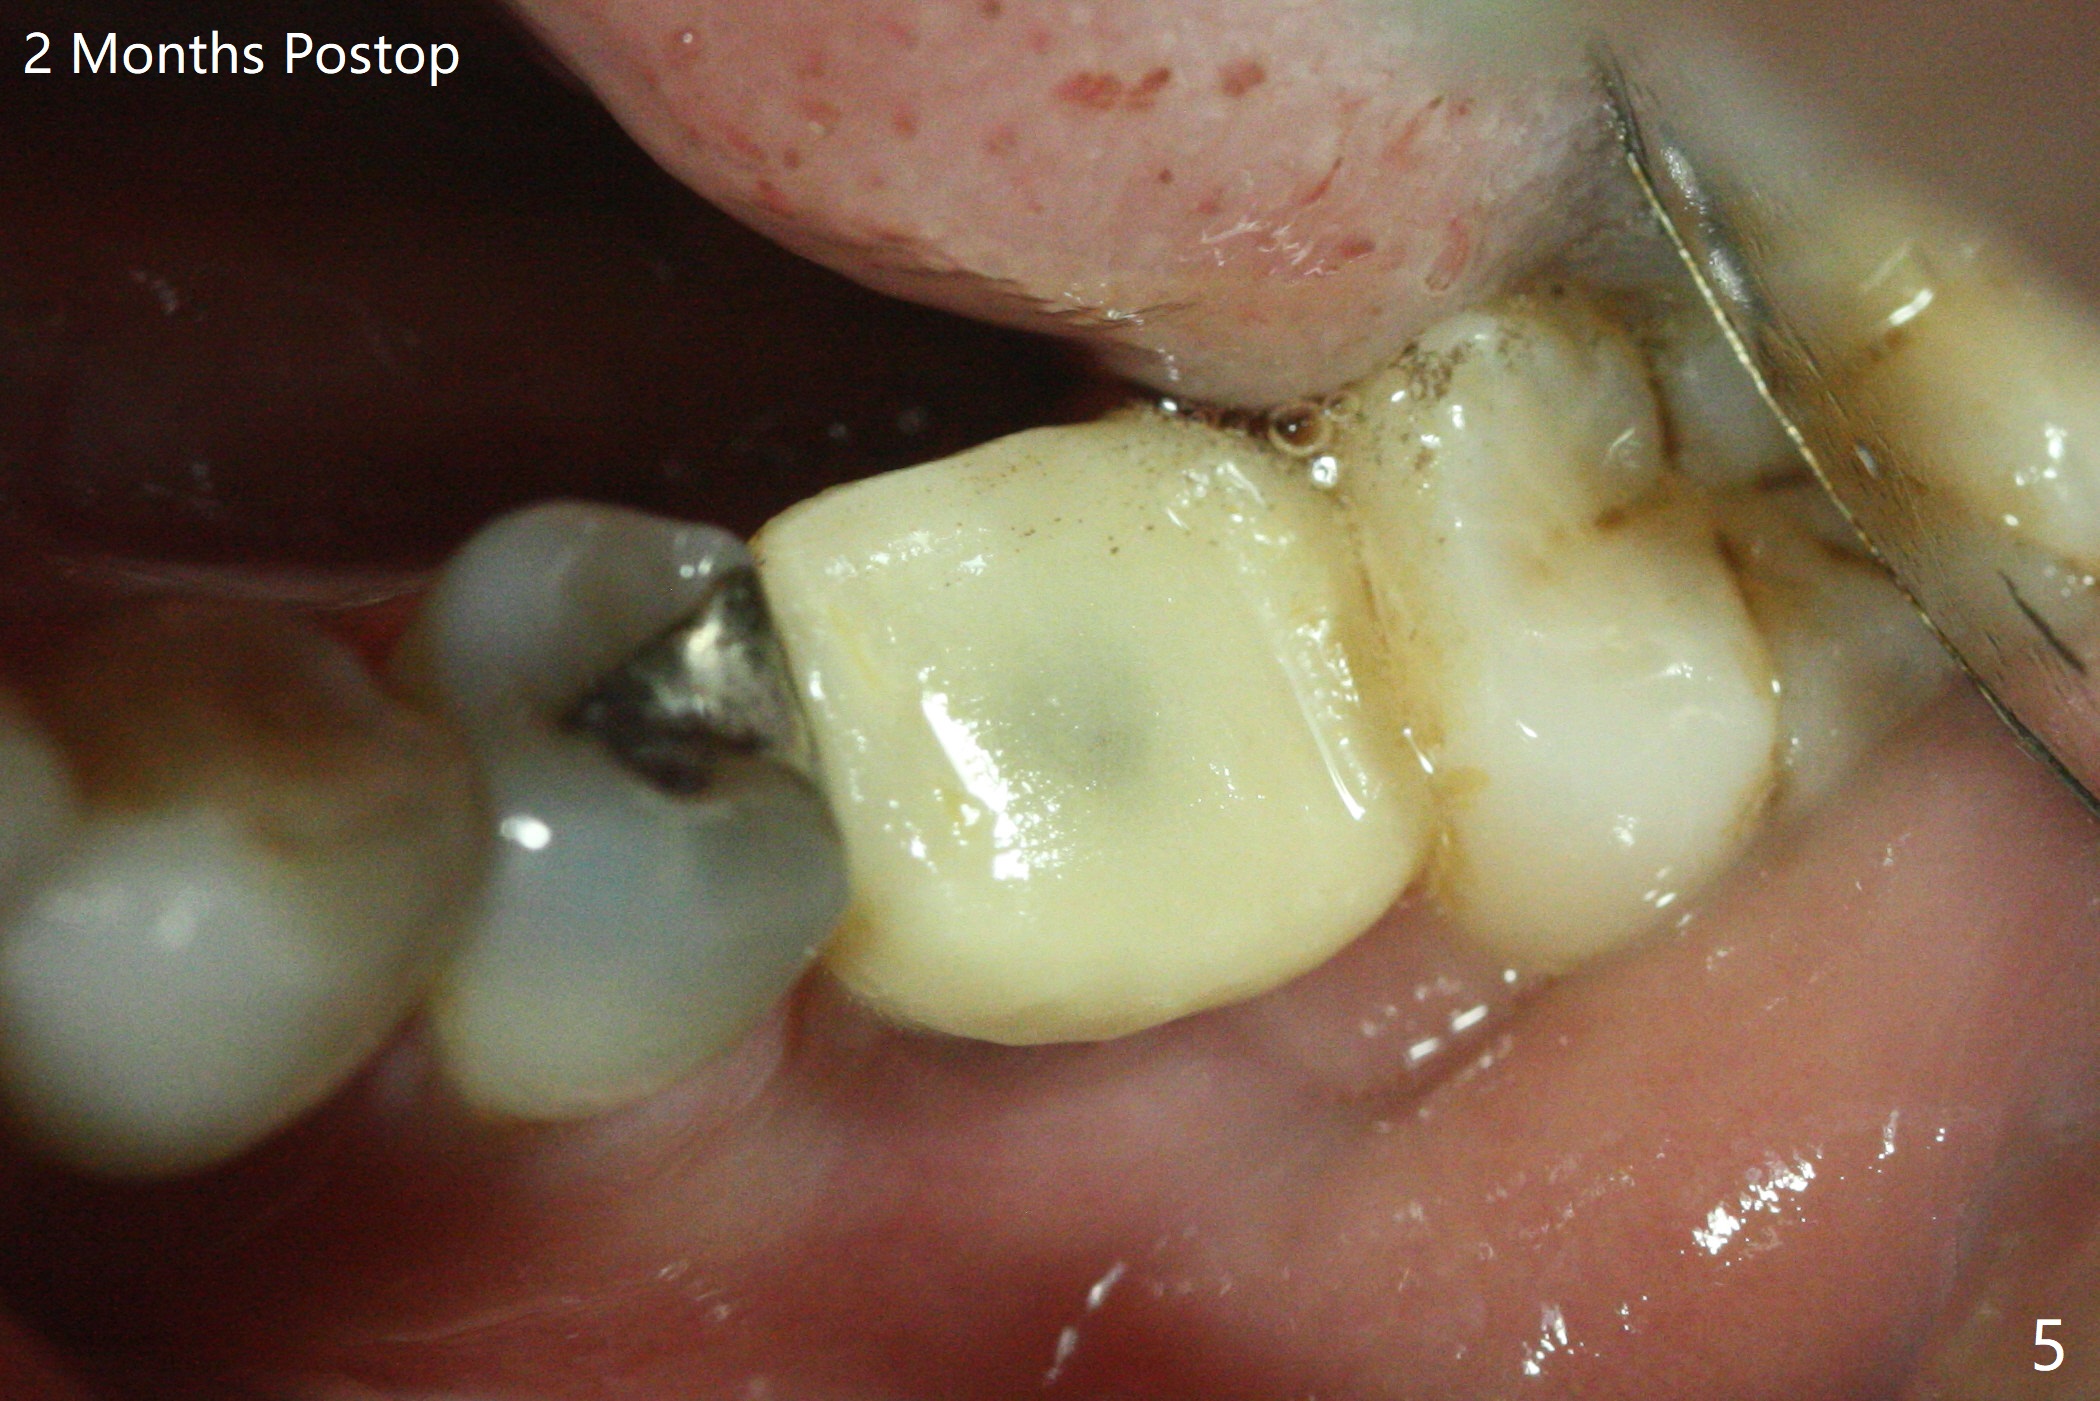

适当更改导板(为两段式接近圆柱状植体设计)钻洞顺序(根尖钻头小,而一段式植体根尖特别尖),5x14毫米一段式软组织水平植体植入,扭力大约35Ncm(图一),略微种深(图二:长箭头)后,磨短基台(与图一对比;左上6伸长),颊侧,远中,舌侧边缘降低(图二,三:<;增加基台高度,提高牙冠固位),制作临时牙冠(图四:P),主要目的将近中牙龈推向近中(图三:空箭头),暴露近中基台边缘,以后好取模。总之,一段式植体需要考虑临时修复。术后两个月临时牙冠和周围牙龈正常(图五)。术后4.5月轻度骨质吸收(图六),临床上看不出来螺纹将要暴露,取模。病人抱怨用临时牙冠咀嚼疼痛,不咬后没有不舒服,其实临时牙冠咬合面穿孔,牙龈正常,永久粘固剂没有外溢(图七)。术后4.5-6个月植体周围骨质吸收(图六,七)。牙槽嵴处钻洞应与植体直径一样才能减少骨质吸收。